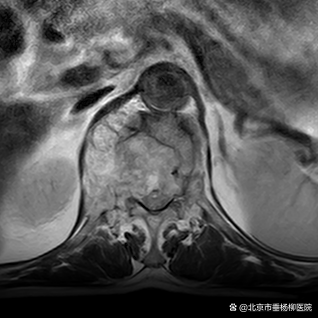

原来在一年前,黄老因罹患肾脏肿瘤行左肾切除术,但术后病理不详。脊柱外科(骨四科)主任姜树东在得知这一情况后,立即为患者完善胸腰椎核磁共振检查。结果提示T12椎体骨质破坏,结构不完整,向后压迫硬膜囊,椎管狭窄,脊髓受压;周围软组织肿胀;考虑病理性骨折(T12),脊柱转移瘤可能性大。随后,再行T12椎体穿刺活检术。同时患者家属提供了患者的既往病历:左肾肿瘤符合透明细胞癌。

▲术前检查

椎骨活检病理结果显示:(T12椎体内组织)送检少许破碎骨组织、多量纤维结缔组织及纤维素渗出坏死组织。纤维结缔组织部分间质疏松水肿,部分区域细胞密集,局灶可见透明细胞浸润。结合病史及免疫组化结果,符合肾透明细胞癌转移。